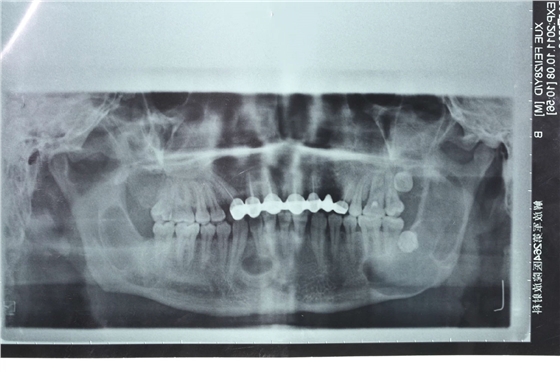

患者男性,主因左面部反復(fù)腫脹半年余,就診后行全景片檢查,發(fā)現(xiàn)下頜骨多發(fā)性囊腫,初步診斷為多發(fā)性頜骨囊腫綜合征,安排住院手術(shù)。